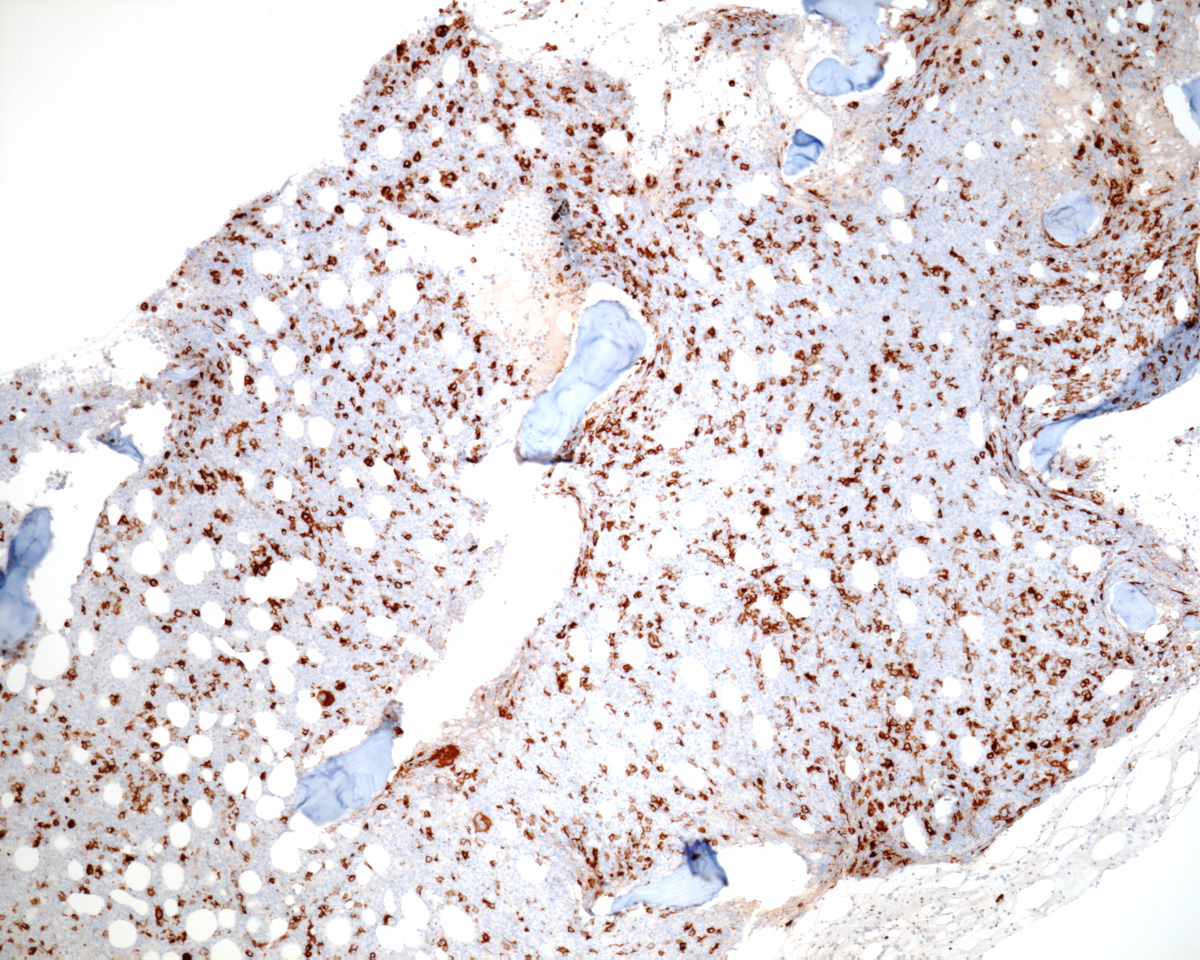

Immunohistochemical stains showed marked increase of megakaryocytes, including numerous small, monolobated forms, which are strongly positive for CD61. CD34 and CD117 highlight increased immature cells, approximately 10% of the nucleated marrow elements. Reticulin shows mild diffuse increase in fiber deposition. An iron stain shows adequate stainable iron. Immunophenotyping by flow cytometry reveals approximately 7% of the total gated events in the dim CD45 positive gate, which coexpress CD34, CD117 and myeloid antigens. A subset of the cells coexpress CD41 and CD61 indicating megakaryocytic lineage.

| Immunohistochemistry CD61 | ![]() |